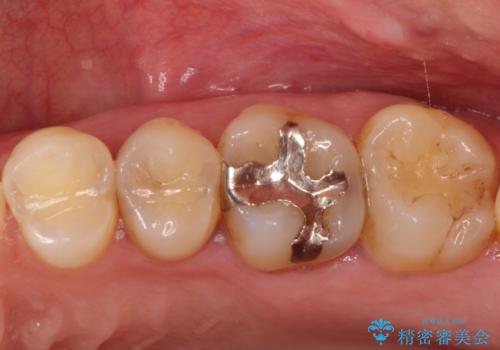

目立つ銀歯と欠けてしまった詰め物 オールセラミッククラウンでの補綴治療

不快感の強い奥歯 オールセラミッククラウンでのむし歯治療